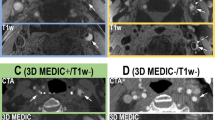

The clot histological spectrum shows the broadest range of possible intensity values in T2w DRIVE images followed by T1w inversion recovery images. (a) Parallel coordinates in the graph display the normalized intensity scales of the applied imaging sequences, and across the scales, in broken lines, each of the 57 thrombi by T1 classification group (single level) in different colors. (b) Likewise, graph with parallel coordinates plot displaying the T2 classification (single level). (c) Schematic overview of the T1 relaxation time clot groups, their neuropathological features, and imaging examples. Groups (or nodes) are in ascending order with regard to fibrin content. Results are expressed as medians and interquartile ranges (IQR). 1The range of normalized intensity values for the MRI sequences is from zero to 1 for T1w TSE SPIR and T2w DRIVE, and from − 1 to 1 for T1w turbo IR. 2For display purposes, the intensity window of T2w DRIVE group 1 was changed manually to allow better visualization. 3P-Values: Kruskal–Wallis Test. T1w Turbo-IR: axial T1-weighted turbo-inversion-recovery; T1w TSE SPIR: axial T1-weighted turbo spin-echo with fat suppression using Spectral Presaturation with Inversion Recovery; T2w DRIVE: axial T2-weighted turbo spin-echo with DRIVen Equilibrium magnetization refocusing.

The parallel coordinates plot in Fig. 3a shows the distribution of the T1 clot groups on the intensity scales for the different MRI sequences used. The T2w images provided the broadest range of intensity values for the clot spectrum (median: 0.274; IQR: 0.137, 0.487; range: 0.071, 0.674), followed by the IR images (median: − 0.131; IQR: − 0.193, − 0.054; range: − 0.317, 0.009), and the T1w TSE with the smallest range (median: 0.230, IQR: 0.215, 0.245 range: 0.193, 0.271). Groups 1 (RBC-rich clots) and 4 (fibrin-rich clots) can be found at the two ends of the clot intensity range on the IR intensity scale, leading to significant differences in imaging (Fig. 3a and c). In contrast, clot histologies converged around a narrow range of T1w TSE intensities. On T2w DRIVE, most of the RBC-rich clots (group 1) lay in a range of higher intensities, separate from the intensity range of other clot groups, grouped at lower T2w intensity values. The parallel coordinates plot for the T2 time clot classification shows a wide intensity range in T2w DRIVE images of thrombi with regard to the iron content (Fig. 3b). In this sense, Fig. 3c shows that in T1w IR images the signal intensity of RBC-rich thrombi (group 1) was the opposite of that of the fibrin-rich clots (group 4) (P < 0.0001), where fibrin-rich clots displayed lower intensity (darker) than RBC-rich thrombi (brighter). In contrast, signal intensity increased with fibrin content in clots in the T2w DRIVE sequence (P < 0.0001). In summary, we found that fibrin rich clots had the longest relaxation times in T2 and in T1, leading to high signal intensity in the T2w DRIVE sequence, and in turn, RBC rich clots had the shortest relaxation times and yielded higher intensity in T1w sequences [supplemental materials: extended Data Fig. 3a–f]. Besides, although there were statistically significant differences in the intensity values for the different clot groups in each sequence, pairwise comparison had difficulty in discriminating between groups 2 (9–28% fibrin) and 3 (28–47% fibrin) in all sequences (all P-values > 0.08 Bonferroni adjusted, see Fig. 4d–f).

MRI sequences: T2w DRIVE followed by T1w turbo IR images provide the widest range of signal intensities for differentiating thrombi

MRI sequence type and parameters and the normalization method used (intensity values from 0 to 1 for T1w TSE and T2w DRIVE and from − 1 to 1 for T1w IR images) are described in the Methods section. Unless otherwise specified, we grouped the clots for further analysis using the T1 classification tree for primary imaging biomarkers.